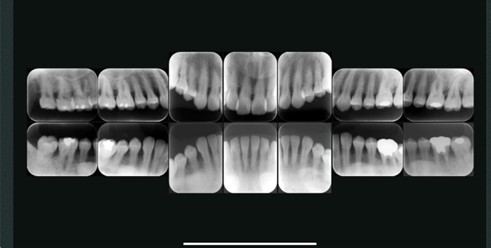

5.デンタルX線撮影(口内法)

- 10枚法(フルマウス撮影)

上下の前歯・奥歯を含む10枚のレントゲン画像を撮影する方法です。歯周病の進行具合や歯の根の状態、歯槽骨の状態を詳しく診断できます。特に、歯周病が気になる方や、複数の歯の治療計画を立てる際に有効です。

10枚法